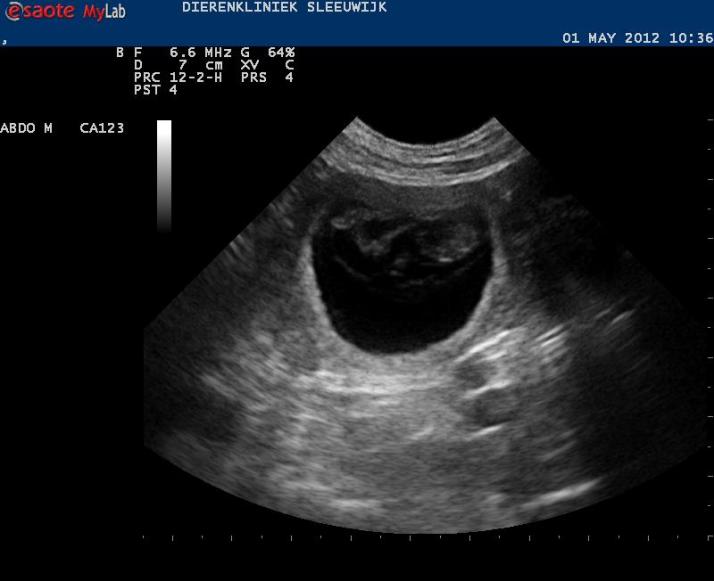

De afspraak voor de echo is gemaakt, ik hoop dat we begin volgende week het eerste bewijs van leven kunnen tonen.

In deze week veranderen de pupjes weer een heleboel: van ‘gekkootjes’ worden het steeds meer pupjes. De organen zijn bijna ‘af’. Zaken als tanden, snorharen, tenen en nagels worden duidelijker. De ogen krijgen oogleden. Het huidpigment wordt aangelegd: als we nu binnenin konden kijken zouden we kunnen zien hoeveel zwarte en hoeveel bruine pupjes Alba gaat krijgen, en of ze aftekeningen hebben.

Aan het eind van de week zijn ze 30 mm groot. De hoeveelheid vruchtwater neemt ook toe.